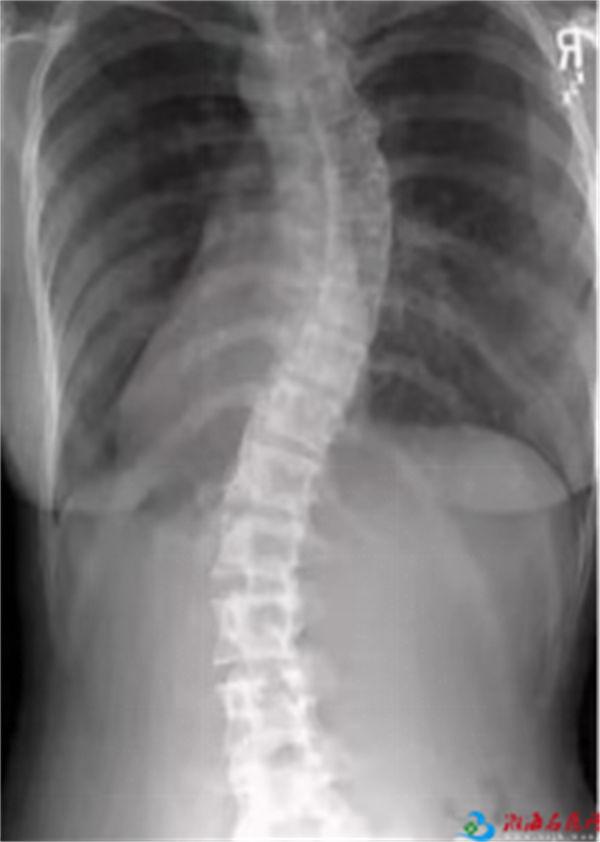

青少年脊柱侧弯影响患者的外观形象,高低肩、剃刀背、代偿性的长短腿。

脊柱侧弯会导致胸腹器官压迫,限制心肺功能和胃肠功能。